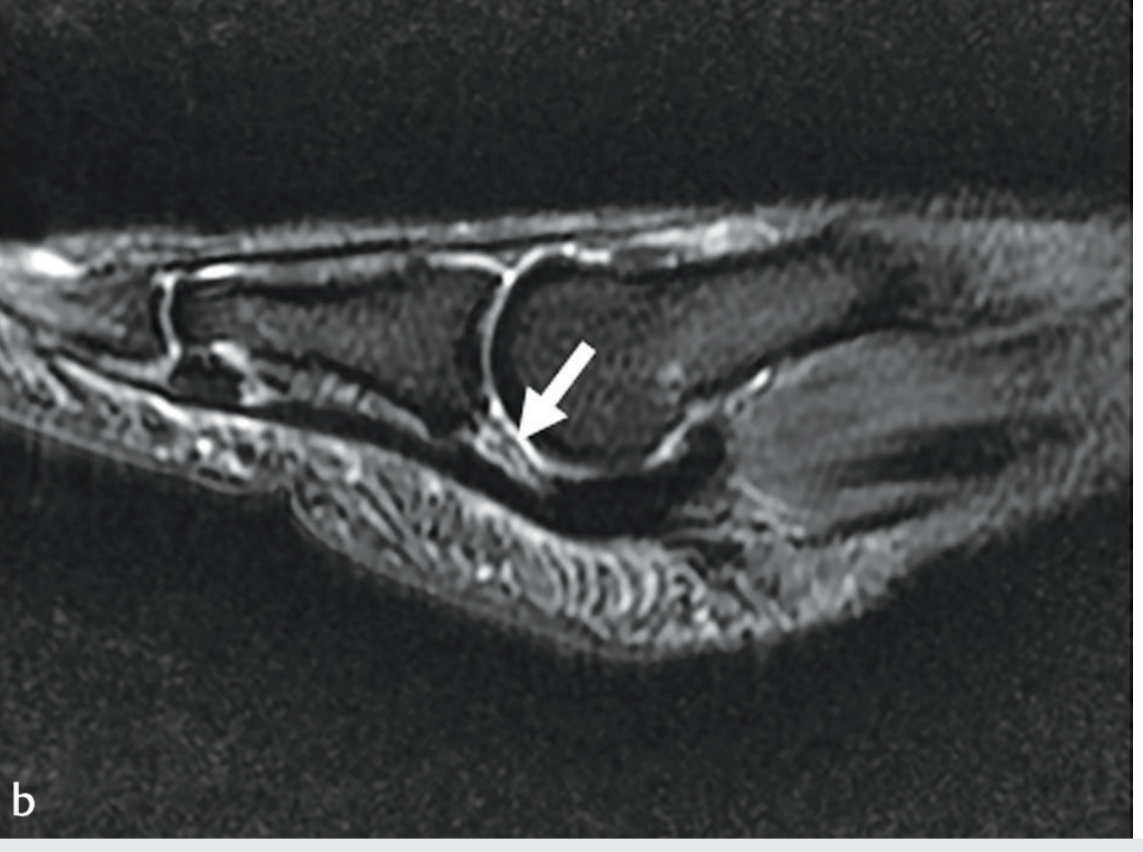

MRI appearance of plantar plate injury:

Sagittal PDFS MRI showing increased signal (arrow) at the distal plantar plate consistent with injury; plate displaced proximally

Sagittal MRI showing increased signal at the distal plantar plate (arrow) consistent with tear; the plate is displaced proximally — Imaging Anatomy: Bones, Joints, Vessels & Nerves